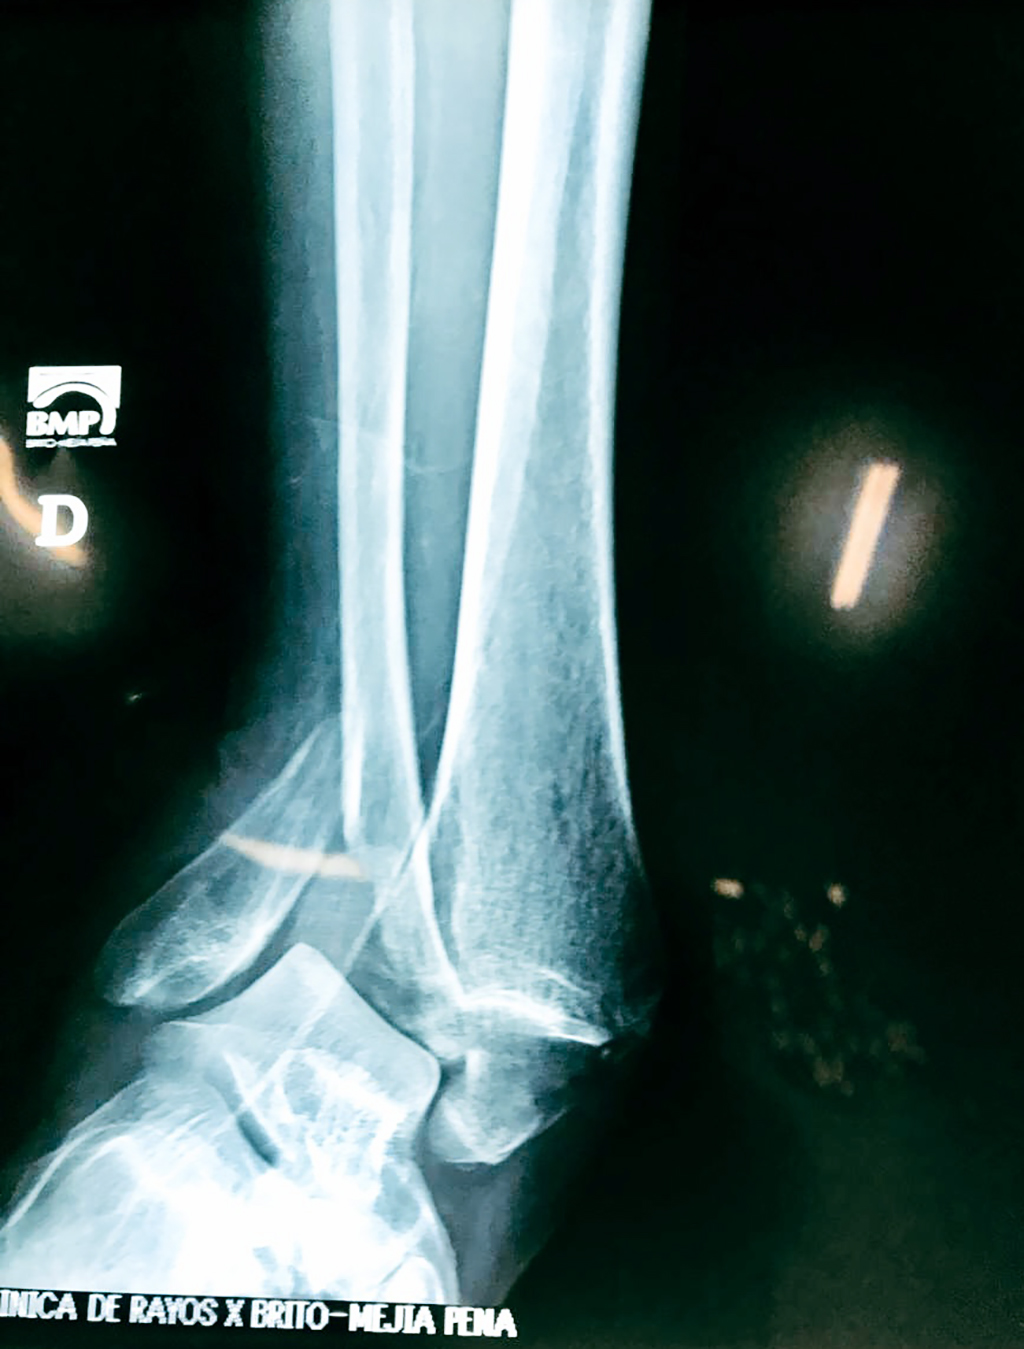

Una fractura de tobillo es la rotura de uno o más de los huesos del tobillo. Estas fracturas pueden ser:

- Los extremos de los huesos están desalineados entre sí (desplazados).

- La fractura se extiende hasta la articulación del tobillo (fractura intra-articular).

- Los tendones o ligamentos (tejidos que sujetan los músculos y los huesos entre sí) están rotos.